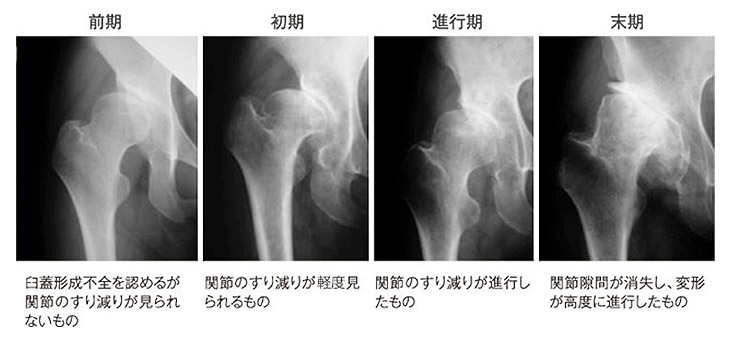

診断としては、レントゲン写真で行うことが可能です。

レントゲン写真では軟骨の厚さや状態を示す関節の隙間の広さ、骨の位置関係、変形などを確認することができます。

それぞれの程度により変形性関節症の進み具合を知ることができます。